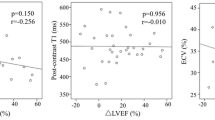

Associations between ECV and LVEDd with AB in DCM

Out of all the parameters that differentiated patients with and without AB (with p < 0.10), only indexed LVEDd and the global ECV were found to be independently associated with AB (Table 3). The ECV had a higher diagnostic yield (p = 0.04) of discriminating AB presence (AUC 0.713, 95%CI 0.598–0.827; p < 0.001) than indexed LVEDd (AUC 0.62, 95%CI 0.504–0.735; p = 0.04) The proposed cut-off point of ECV of 31.05% had a higher specificity and sensitivity than indexed LVEDd cut-off point of 33.27 mm/m2 (sensitivity/specificity: 55%/79% vs. 44%/78%, respectively). The proposed cut-off points of ECV and indexed LVEDd had the highest accuracy (72% vs. 64%, respectively) (Fig. 2). An increase in ECV by 1% increases the risk of AB occurrence by 12%. ECV > 31.05% increased AB sixfold (HR 6.19; 95%CI 1.95–19.63; p = 0.002) with adjustment for the presence of hypertension, systolic blood pressure, LV end-diastolic indexed diameter and loop diuretics’ daily dosage.